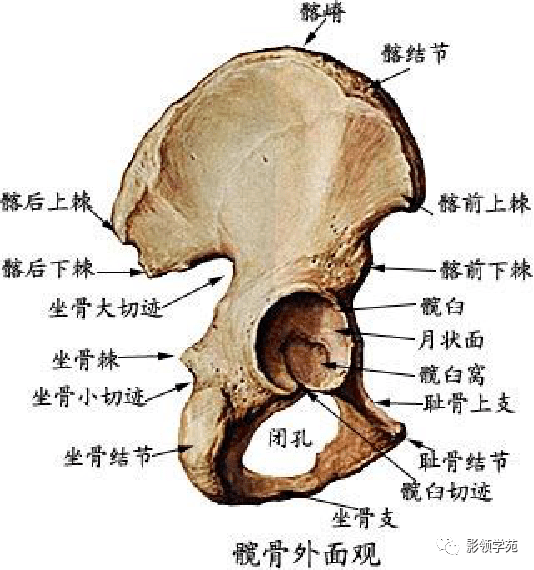

骨骼系统

骨骼系统